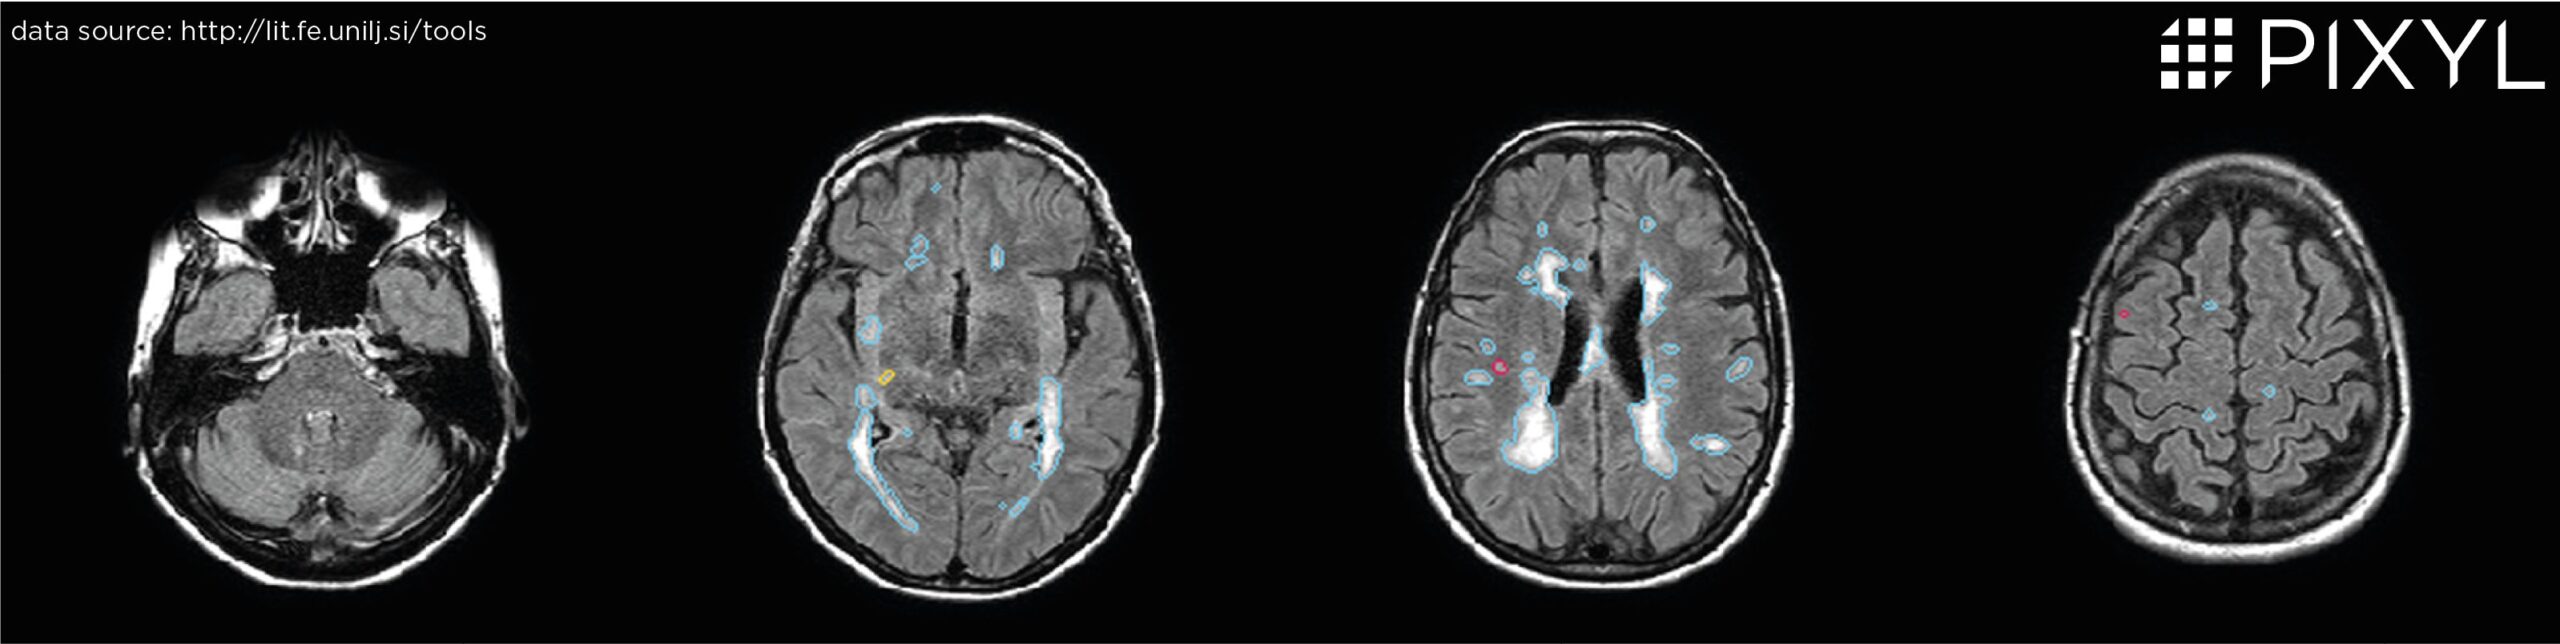

Quantification in MS

Mrs MUÑOZ RAMÍREZ

Pixyl